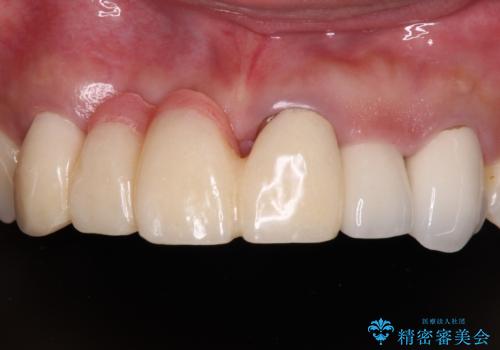

- 前歯を2本抜歯した後に装着した仮歯が長く見えるのが気になるとのことで来院された患者様です。

前医では、歯肉の位置に相当する部分を、歯肉に近い色とすることで歯の長さが揃っているようにカムフラージュする治療が提案され、仮歯もそのようになっていました。